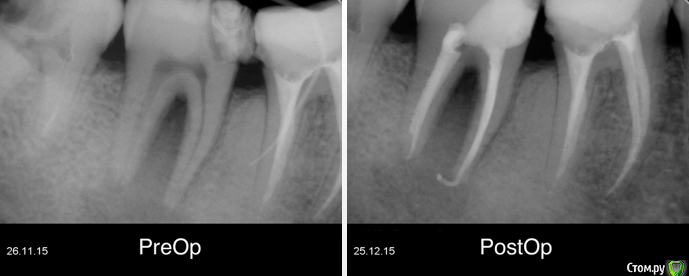

Гарриевич Опубликовано 22 декабря, 2017 Поделиться Опубликовано 22 декабря, 2017 (изменено) админы, если уже создавал такую тему, объедините пожалуйста абсолютно бессимптомный зуб, пациента ничего не беспокоило кроме... да нет, вообще ничего не беспокоило. Лечение в два посещения через гидроксид кальция. Обтурация инжектором. Будут вопросы спрашивайте, каких то еще особенностей сразу не вспомню PS сроки наблюдения 10 месяцев и два года Изменено 22 декабря, 2017 пользователем Гарриевич 8 Ссылка на комментарий

Гарриевич Опубликовано 23 декабря, 2017 Автор Поделиться Опубликовано 23 декабря, 2017 Скорее всего гутту съехала пока снимки делали. Вложения гидроокиси на 2 недели. В данном случае порошок чистого гидроксида кальция замешанный с водой непосредственно перед внесением. Также испольщую кальцетин технодентовский Ссылка на комментарий

Гарриевич Опубликовано 15 сентября, 2019 Автор Поделиться Опубликовано 15 сентября, 2019 полное заживление, осмотр через 3 года 5 Ссылка на комментарий